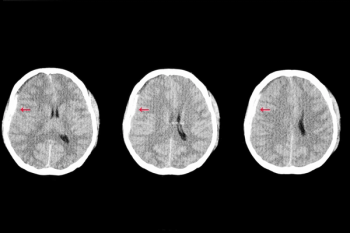

Viz.ai said the Viz Subdural Hematoma (SDH) artificial intelligence (AI) algorithm provides automatic detection of acute and chronic subdural hemorrhages, facilitating timely triage and treatment of patients.

Artificial intelligence (AI) accurately diagnosed 79 percent of proximal large vessel occlusions with an ipsiversive gaze deviation on non-contrast computed tomography (CT), according to new research findings presented recently at the Society of Neurointerventional Surgery’s (SNIS) 19th Annual Meeting in Toronto.

RapidAI’s Rapid Hyperdensity tool reportedly allows quicker assessment of hyperdense tissue in the brain via non-contrast computed tomography (CT) scans.